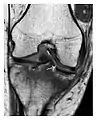

Figure 7: Fatigue fracture of the talus in a 25-year-old male basketball player with right hind foot and ankle pain, without history of trauma, and a normal initial radiograph (not shown). (a) One-month followup lateral radiograph shows normal appearance. (b) Sagittal T1-weighted MRI shows an irregular fracture line (arrow) within an ill-defined area of hypointensity corresponding to bone marrow edema.[1]